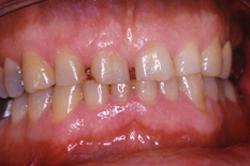

Préparation et empreinte des dents mandibulaires. Les dents vivantes sont conservées pulpées. Les limites des préparations sont supra-gingivales.

Couronnes céramo-céramiques. Réalisation prothétique Claude VALTIN (Paris).

Les 14 Couronnes céramo-céramiques mandibulaires collées.